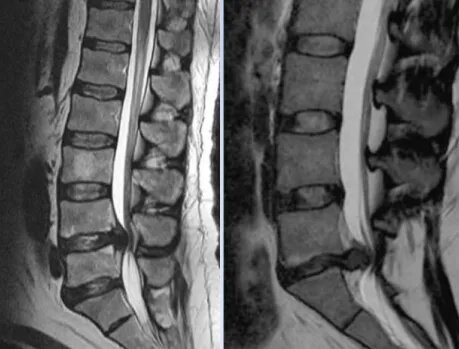

Развитие синдрома связано со сдавлением конского хвоста в соответствующей части позвоночника. Основной причиной этого являются дегенеративно-дистрофические изменения позвоночника, в частности грыжи межпозвонковых дисков. Фактически соответствующие симптомы развиваются в 1–2% поясничных грыж.

Конским хвостом называют пучок нервов, отходящих от места, где спинной мозг заканчивается концевой (терминальной) нитью. Этот пучок начинается на уровне поясницы от четырех нижних поясничных, пяти крестцовых и одного копчикового спинномозговых корешков, а затем конусообразно расходится, обеспечивая передачу нервных импульсов в ноги и органы малого таза.